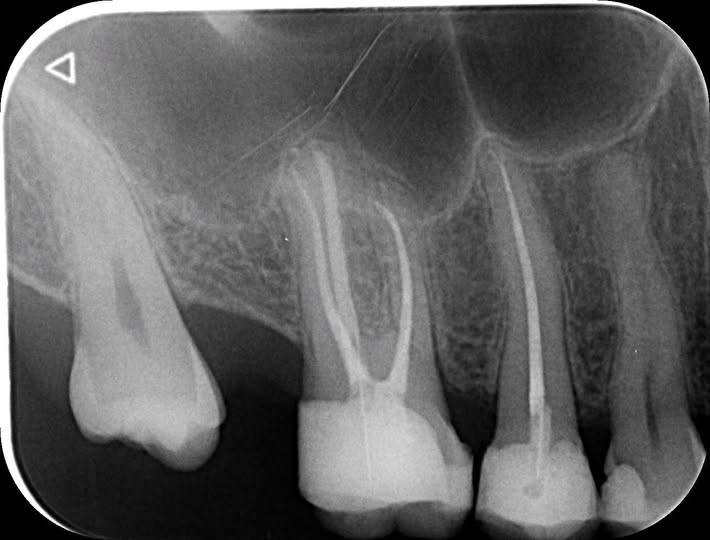

In this clinical case, Dr. Ciprian Hanus (@endobrainiac) demonstrates the treatment of tooth 2.4 using the Ino-Shaper rotary file system by Rogin. As an experienced endodontist, Dr. Hanus trusts this system for its versatility — particularly its adaptive motion technology, which allows the files to respond dynamically to the canal anatomy.